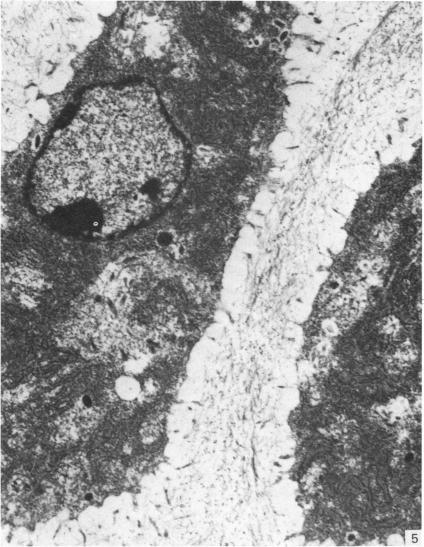

来自矮胖(stm)突变小鼠下颌髁突的异常软骨。

Abnormal cartilage from the mandibular condyle of stumpy (stm) mutant mice.

The mammalian mandibular condyle is composed of secondary cartilage and may thus be susceptible to genes causing achondroplasia and which result in abnormal++ primary cartilage formation. This paper describes the secondary cartilage in the mandible of the stumpy achondroplastic mutation in the mouse: both primary and secondary cartilage are affected by the gene.

哺乳动物的下颌髁由继发性软骨组成,因此可能易受导致软骨发育不全并致使初级软骨形成异常的基因影响。本文描述了小鼠短粗型软骨发育不全突变体下颌骨中的继发性软骨:初级软骨和继发性软骨均受该基因影响。